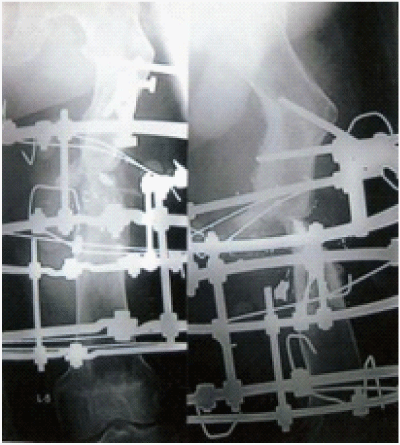

Figure 3 1st post op with Ilizarov in situ.

Figure 4 Monofocal corticotomy of left tibia with fibular osteotomy.

Figure 5 Radiograph of left tibia with distraction osteogenesis.